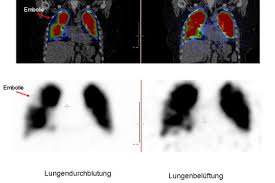

Nuklearmedizinische Diagnostik Nuklearmedizin Universitatsklinik Fur Nuklearmedizin

Nuklearmedizinische Diagnostik Nuklearmedizin Universitatsklinik Fur Nuklearmedizin from www.nukmed.insel.ch